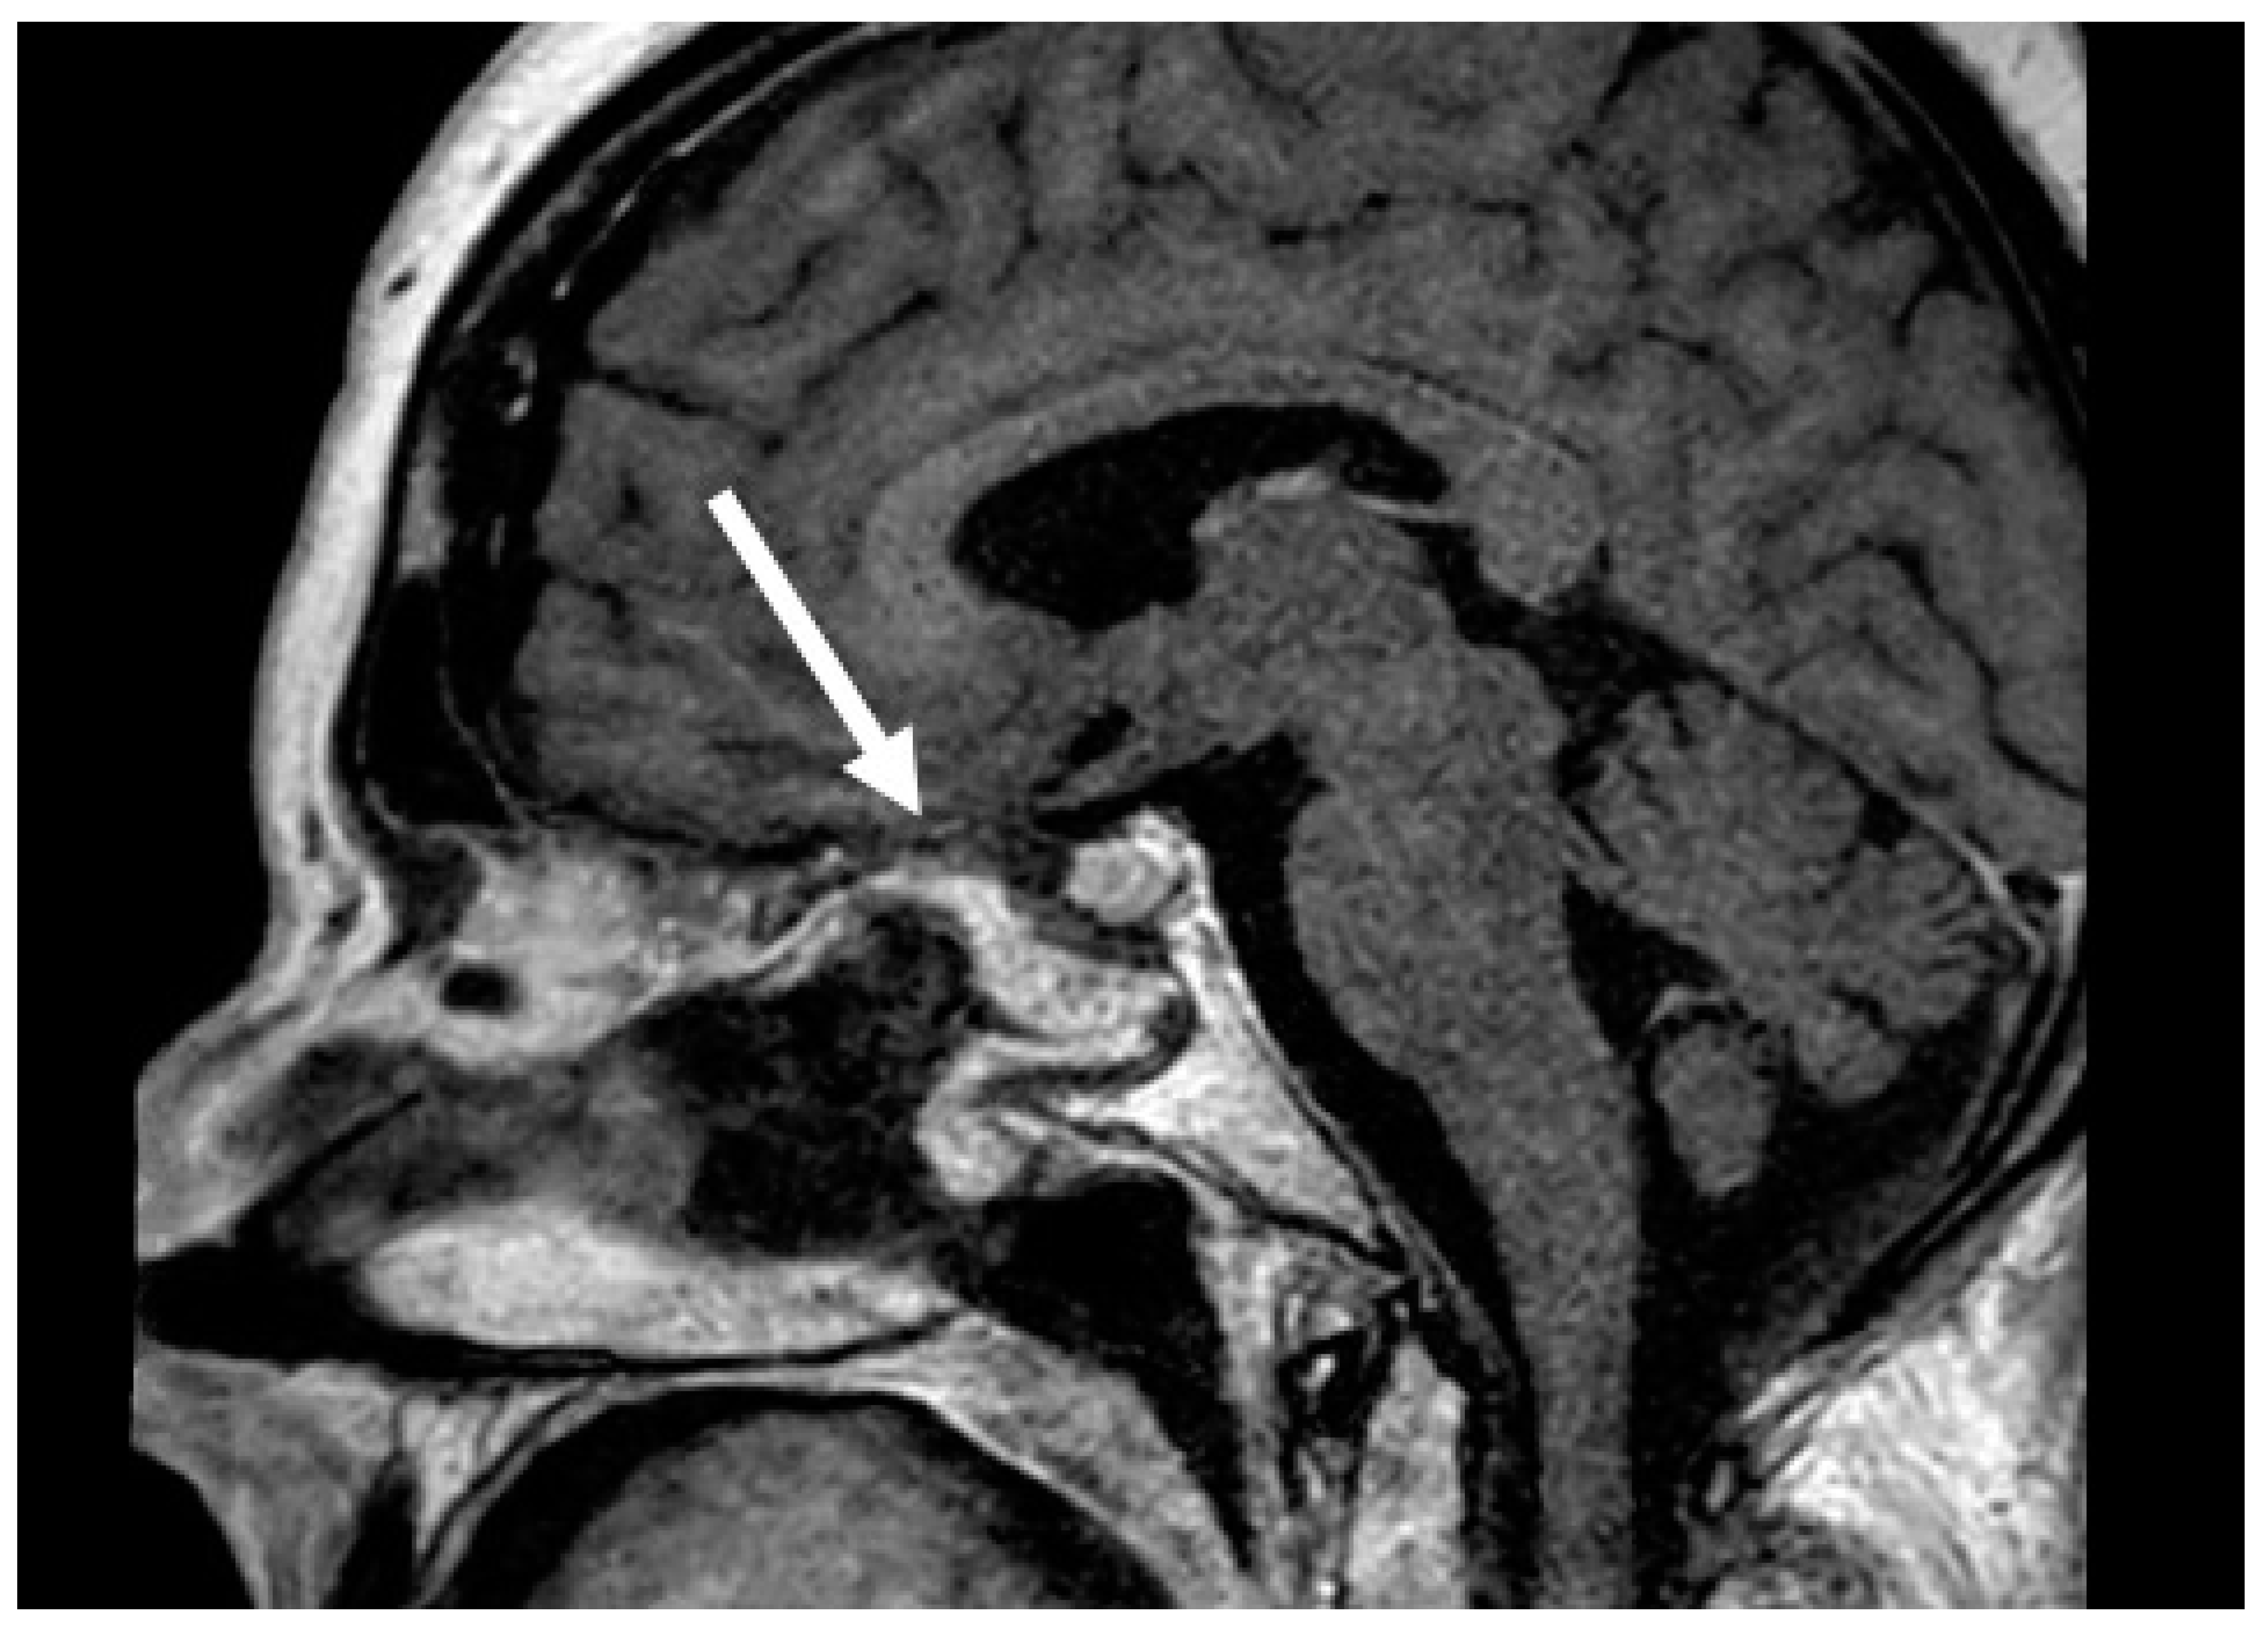

The nasoseptal flap was first described in 2006 and has significantly changed the practice of skull base surgery by decreasing rates of postoperative CSF leaks and meningitis [2,17]. This provides a large, vascularized graft to repair skull base defects and is considered the workhorse of skull base reconstruction because it can be used to reconstruct all regions of the central skull base. Among patients with high-flow intraoperative CSF leaks, nasoseptal flap reconstruction typically results in a postoperative CSF leak of 5% [7]. Compared to reconstruction with free grafts for large dural defects, nasoseptal flaps demonstrate a significant benefit in reducing postoperative CSF leaks [2]. This flap is also versatile and can be tailored for specific defects. The standard flap is raised along the septum with the inferior incision at the most inferior aspect of the septum at the nasal floor. However, an extended nasoseptal flap can also be harvested, which includes the nasal floor mucosa to the inferior meatus to increase the area of the flap [18]. Figure 2 demonstrates a well-healed nasoseptal flap on postoperative T1 post-contrast MRI images that were used for skull base reconstruction after pituitary mass resection. MRI images can be helpful in the postoperative nasoseptal flap assessment if there is a question of flap viability and if it is not clinically feasible to perform a debridement for direct inspection. The nasal flap is also versatile and can reconstruct defects from the lower portion of the posterior table of the frontal sinus to the clivus and foramen magnum. Despite the inherent reconstructive benefits of the nasoseptal flap, there is associated donor site morbidities, including nasal crusting, drainage, decreased olfaction, septal perforation, and nasal dorsum collapse [19,20]. The reverse nasoseptal flap is a technique that has been recently described to decrease the morbidity of the NSF with reports of decreased crusting and patient reported nasal deformities [20,21]. However, this is accompanied by the limitation of preventing use of the contralateral septal mucosa for another nasoseptal flap. Another option to decrease crusting after nasoseptal flap harvest is securing a free mucosal graft onto the exposed septum to facilitate remucosalization.

Figure 2. Postoperative T1 post-contrast sagittal MRI images of a well-healed nasoseptal flap (arrow).